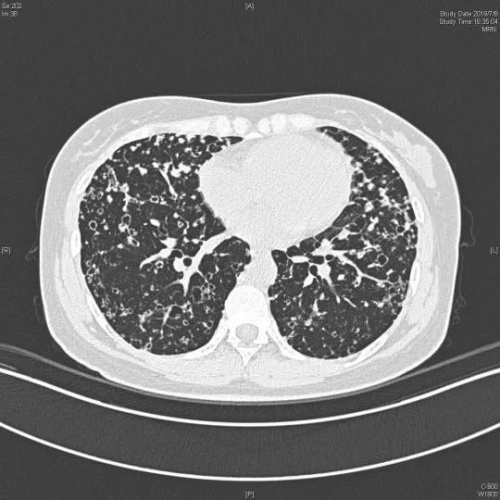

核心提示:近日,由西安工業(yè)大學(xué)趙妙梅、趙何超團(tuán)隊(duì)主導(dǎo)的多學(xué)科交叉多專業(yè)融合的“火眼金睛”項(xiàng)目在數(shù)字醫(yī)學(xué)影像診斷領(lǐng)域取得重大進(jìn)展近日,由西安工業(yè)大學(xué)趙妙梅、趙何超團(tuán)隊(duì)主導(dǎo)的多學(xué)科交叉多專業(yè)融合的“火眼金睛”項(xiàng)目在數(shù)字醫(yī)學(xué)影像診斷領(lǐng)域取得重大進(jìn)展,該技術(shù)通過開發(fā)“CNN&Transformer”交錯(cuò)融合算法,成功賦能肺部數(shù)字醫(yī)學(xué)影像精準(zhǔn)診斷,為該行業(yè)提供創(chuàng)新解決方案。

該團(tuán)隊(duì)科研攻關(guān)“空洞卷積神經(jīng)網(wǎng)絡(luò)(CNN)”技術(shù)和“動(dòng)態(tài)雙路徑多尺度特征融合(D-DMFF)”技術(shù),研發(fā)了可有效提取肺部HRCT圖像中的局部與全局特征的輕量化模型。該模型通過97740張CT圖像訓(xùn)練和5012張CT圖像的驗(yàn)證后,沒有明顯的過擬合或欠擬合現(xiàn)象,模型訓(xùn)練良好,病灶分辨率從原有的1mm提升至0.625mm,分辨力提升了37.5%,準(zhǔn)確率高達(dá)96.342%。具備低復(fù)雜度和高有效性,能夠更準(zhǔn)確的識(shí)別肺部病變CT圖像。

該項(xiàng)目在試驗(yàn)階段,從醫(yī)生肉眼漏診病人的上萬張HRCT圖像中,額外識(shí)別出100余人,有效降低了漏診率。